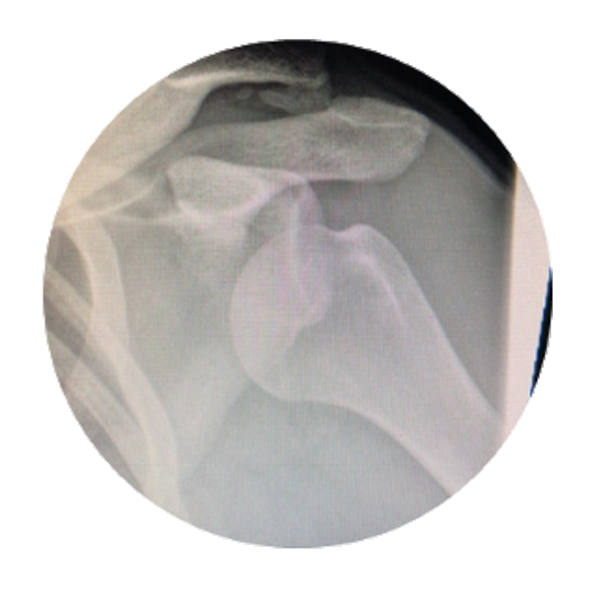

Before surgery, initial Imaging will use different diagnostic tools.

1. X-rays. These will be use scan bones to see if any are broken or fractured. X-rays also are used to scan joints for dislocations or subluxation/separation.